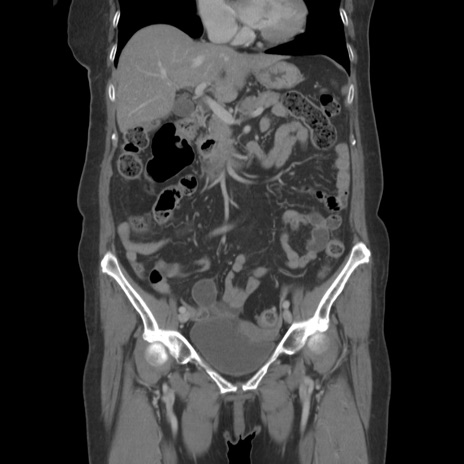

症例19(冠状断像)

【症例】80歳代女性

【主訴】下腹部痛

【現病歴】約8時間前より下腹部痛の出現あり、救急外来受診。

【既往歴】両側付属器切除

【身体所見】意識清明、下腹部正中に手術痕あり、その部位に一致して圧痛と反跳痛あり。腸蠕動音は亢進。

【データ】WBC 9300、CRP 0.15